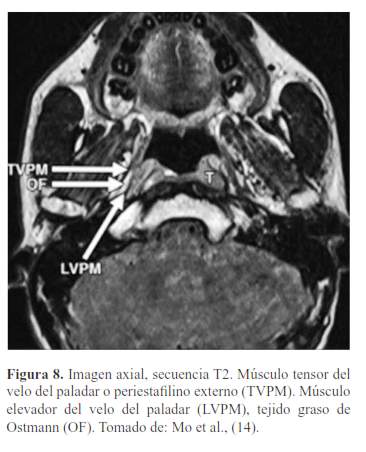

El paladar blando está formado por 5 músculos a cada lado, insertados en el velo, formados de adelante hacia atrás vistas mediante RM (10) (figura 5, figura 6, figura 7, figura 8 y figura 9):

Periestafilino externo o tensor del velo del paladar.